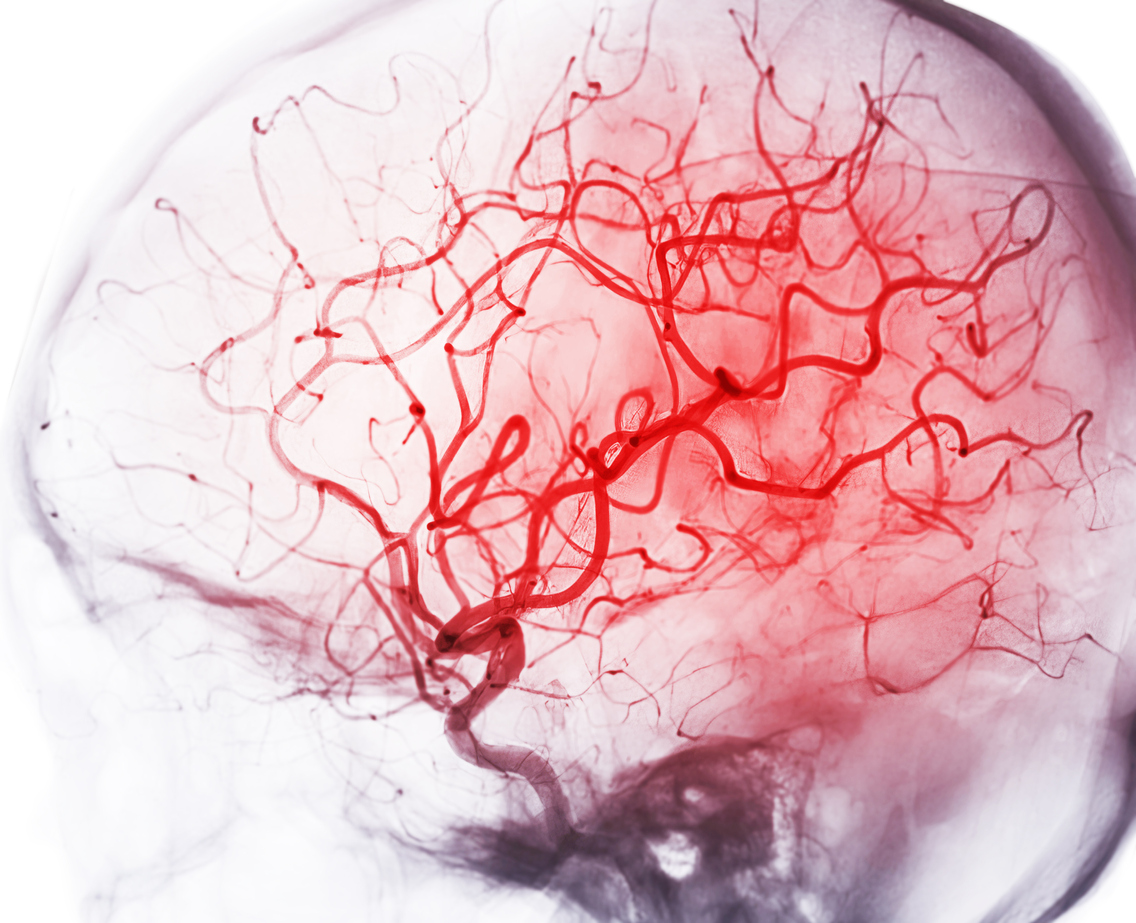

Η αιμορραγία στον εγκέφαλο δεν είναι πάντα απόρροια κάποιου τραυματισμού στο κεφάλι.

Μπορεί να την προκαλέσουν τα ίδια τα αγγεία του εγκεφάλου στην προσπάθειά τους να απαλλαγούν από τα κύτταρα του αίματος που «κολλάνε» στο εσωτερικό τους.

Μια πρώτη στο είδος της μελέτη με επικεφαλής το Πανεπιστήμιο της Καλιφόρνια, Irvine, αποκάλυψε έναν νέο «ένοχο» στον σχηματισμό εγκεφαλικών αιμορραγιών εκτός από τους τραυματισμούς στα αιμοφόρα αγγεία, όπως πίστευαν μέχρι σήμερα.

Οι ερευνητές ανακάλυψαν ότι οι αλληλεπιδράσεις μεταξύ των «γερασμένων» ερυθρών αιμοσφαιρίων με τα τριχοειδή αγγεία του εγκεφάλου μπορεί να οδηγήσουν σε εγκεφαλικές μικροαιμορραγίες.

Τα ευρήματα, που δημοσιεύτηκαν στο Journal of Neuroinflammation, περιγράφουν πώς η ομάδα μπόρεσε να παρακολουθήσει τη διαδικασία με την οποία τα ερυθρά αιμοσφαίρια σταματούν στα τριχοειδή αγγεία του εγκεφάλου και στη συνέχεια να παρατηρήσει πώς συμβαίνει η αιμορραγία.

Οι εγκεφαλικές μικροαιμορραγίες σχετίζονται με μια ποικιλία άλλων καταστάσεων υγείας που εμφανίζονται σε υψηλότερα ποσοστά σε ηλικιωμένους ενήλικες, συμπεριλαμβανομένης της υπέρτασης, της νόσου του Αλτσχάιμερ και του ισχαιμικού εγκεφαλικού.